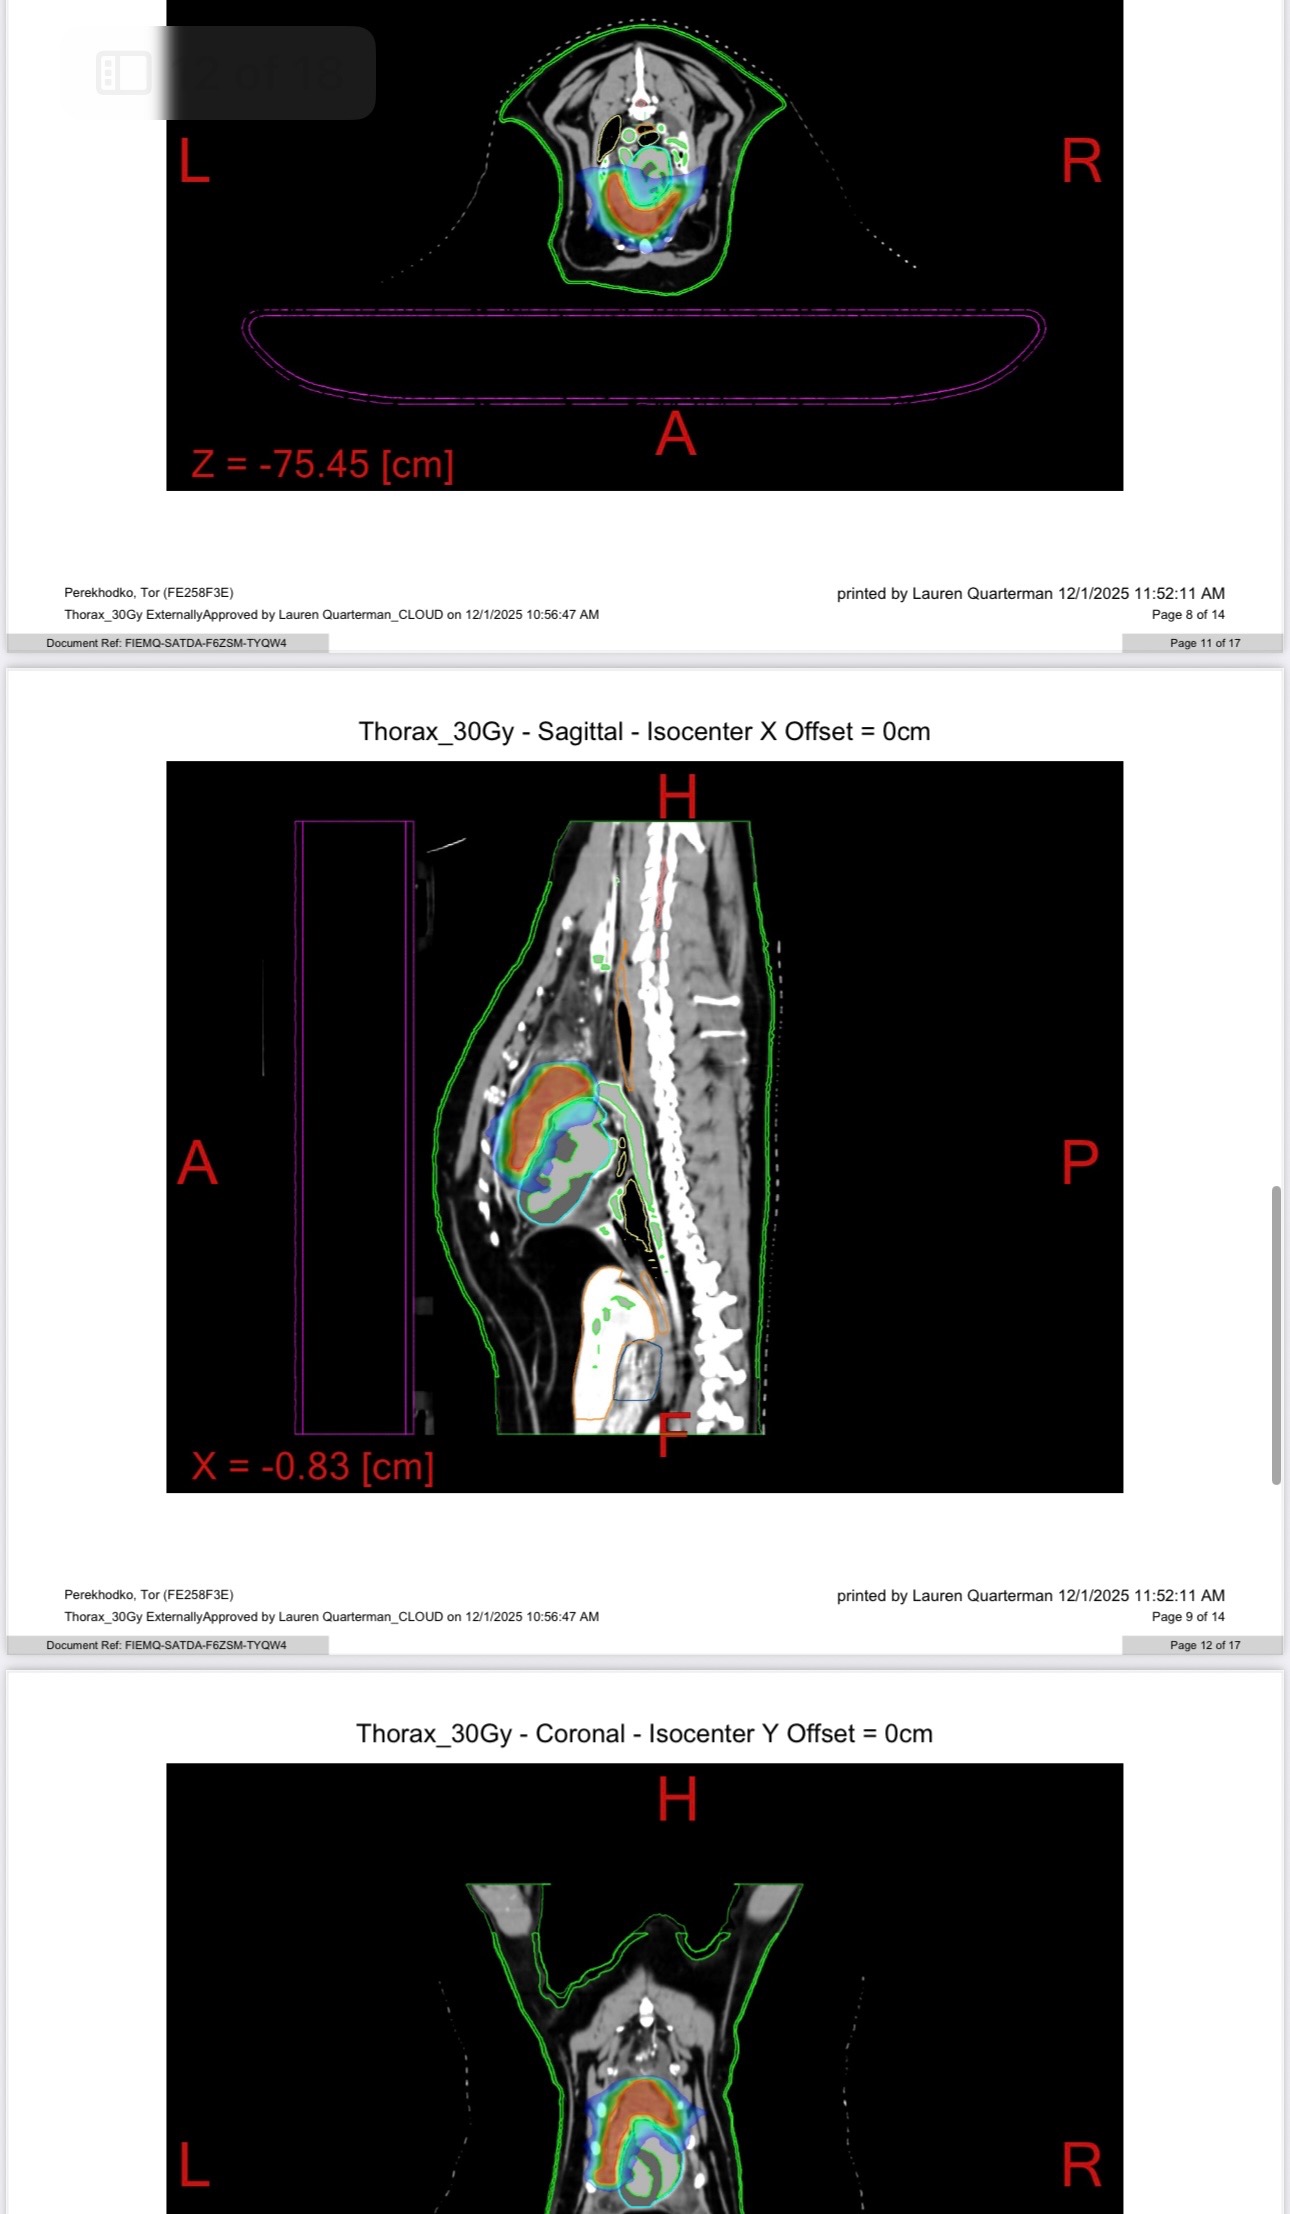

Few weeks ago I found out he has a tumor in his chest that pressing on his heart and lungs. So far we did CT scan, two chest X-rays, two ultrasounds, cytology test, PARR testing, consultation with oncology and surgery.

The CT showed that the tumor is large and invading a major vessel, which makes surgery extremely dangerous. There’s a risk he wouldn’t survive an operation right now.

After consultation with oncologist we decided that the safest way would be radiation.

Tor will start definitive RapidArc radiation therapy next week.